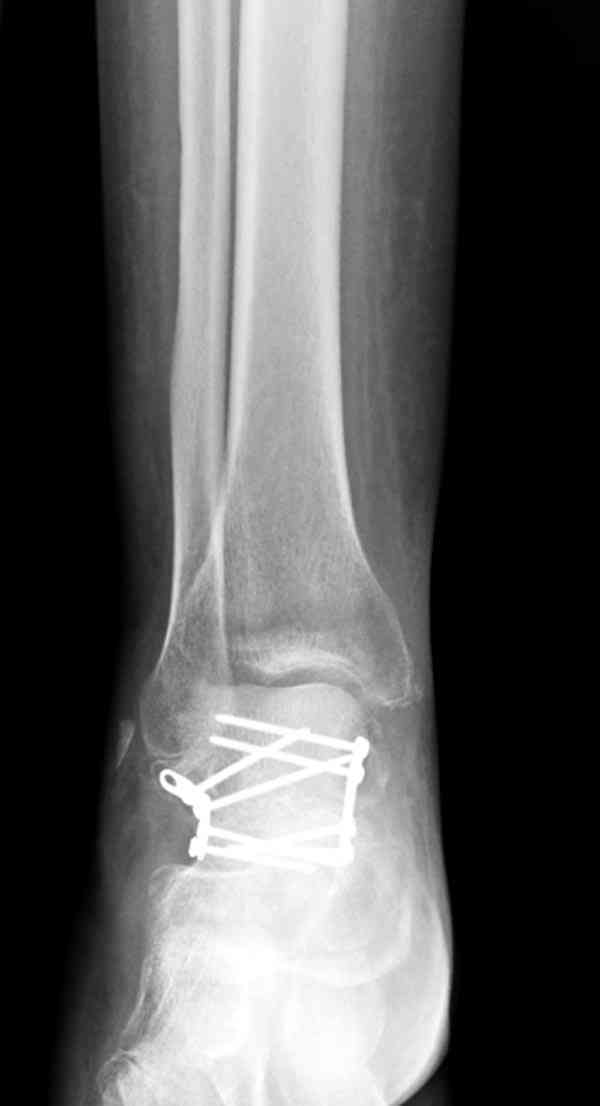

Случай с множественным оскольчатым переломом тарана оперированный из двойного доступа.

Через 2 мес.:

Через 8 мес.:

Через 14 мес.: